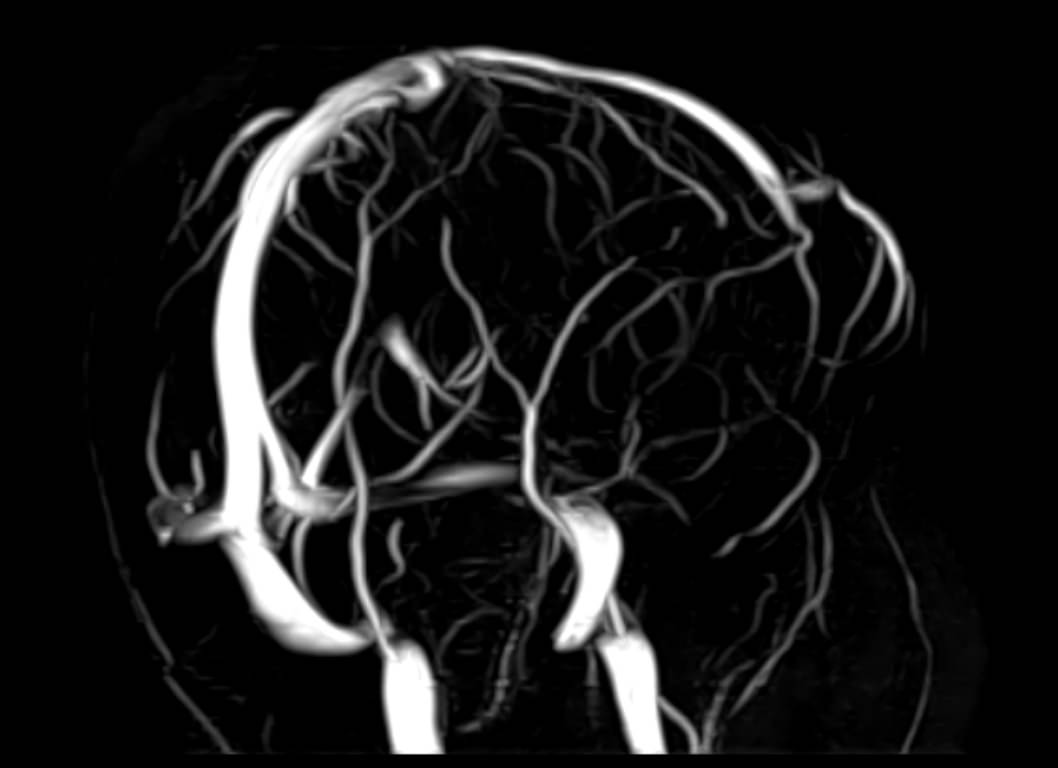

Магнитно-резонансная венография головного мозга позволяет детально изучить особенности анатомического и функциональной состояния венозного русла головы и шеи. С помощью данного исследования можно исключить многие серьезные заболевания сосудов головного мозга и начать своевременное лечение.